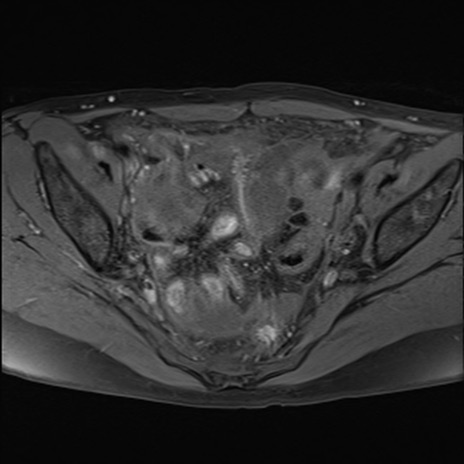

MRI(4日後)

T1WI(横断像)